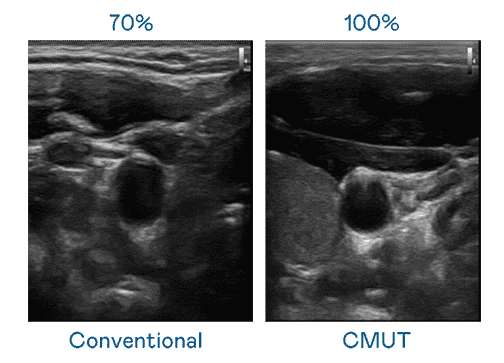

CMUT 技术是一种用电容式微机电元件来产生超音波讯号的技术。。。。与传统 PZT 压电式技术相比,,CMUT 频宽增加 30%,,更宽频的超音波讯号让影像解析度大幅提升,,是实现高影像品质医疗超音波扫描、、、促进精准医疗发展的关键技术。。。。

大频宽带来超清晰影像

超音波影像的解析度高低,,首先取决于探头能发出的讯号频宽。。。。云顶国际8588yd CMUT 可提供高清晰的超音波讯号,,,,提供高频宽、、、、高灵敏度、、、影像纹理细节更高的超音波影像,,,,协助医护人员缩短影像判读时间及利用精准的医疗影像进行诊断。。